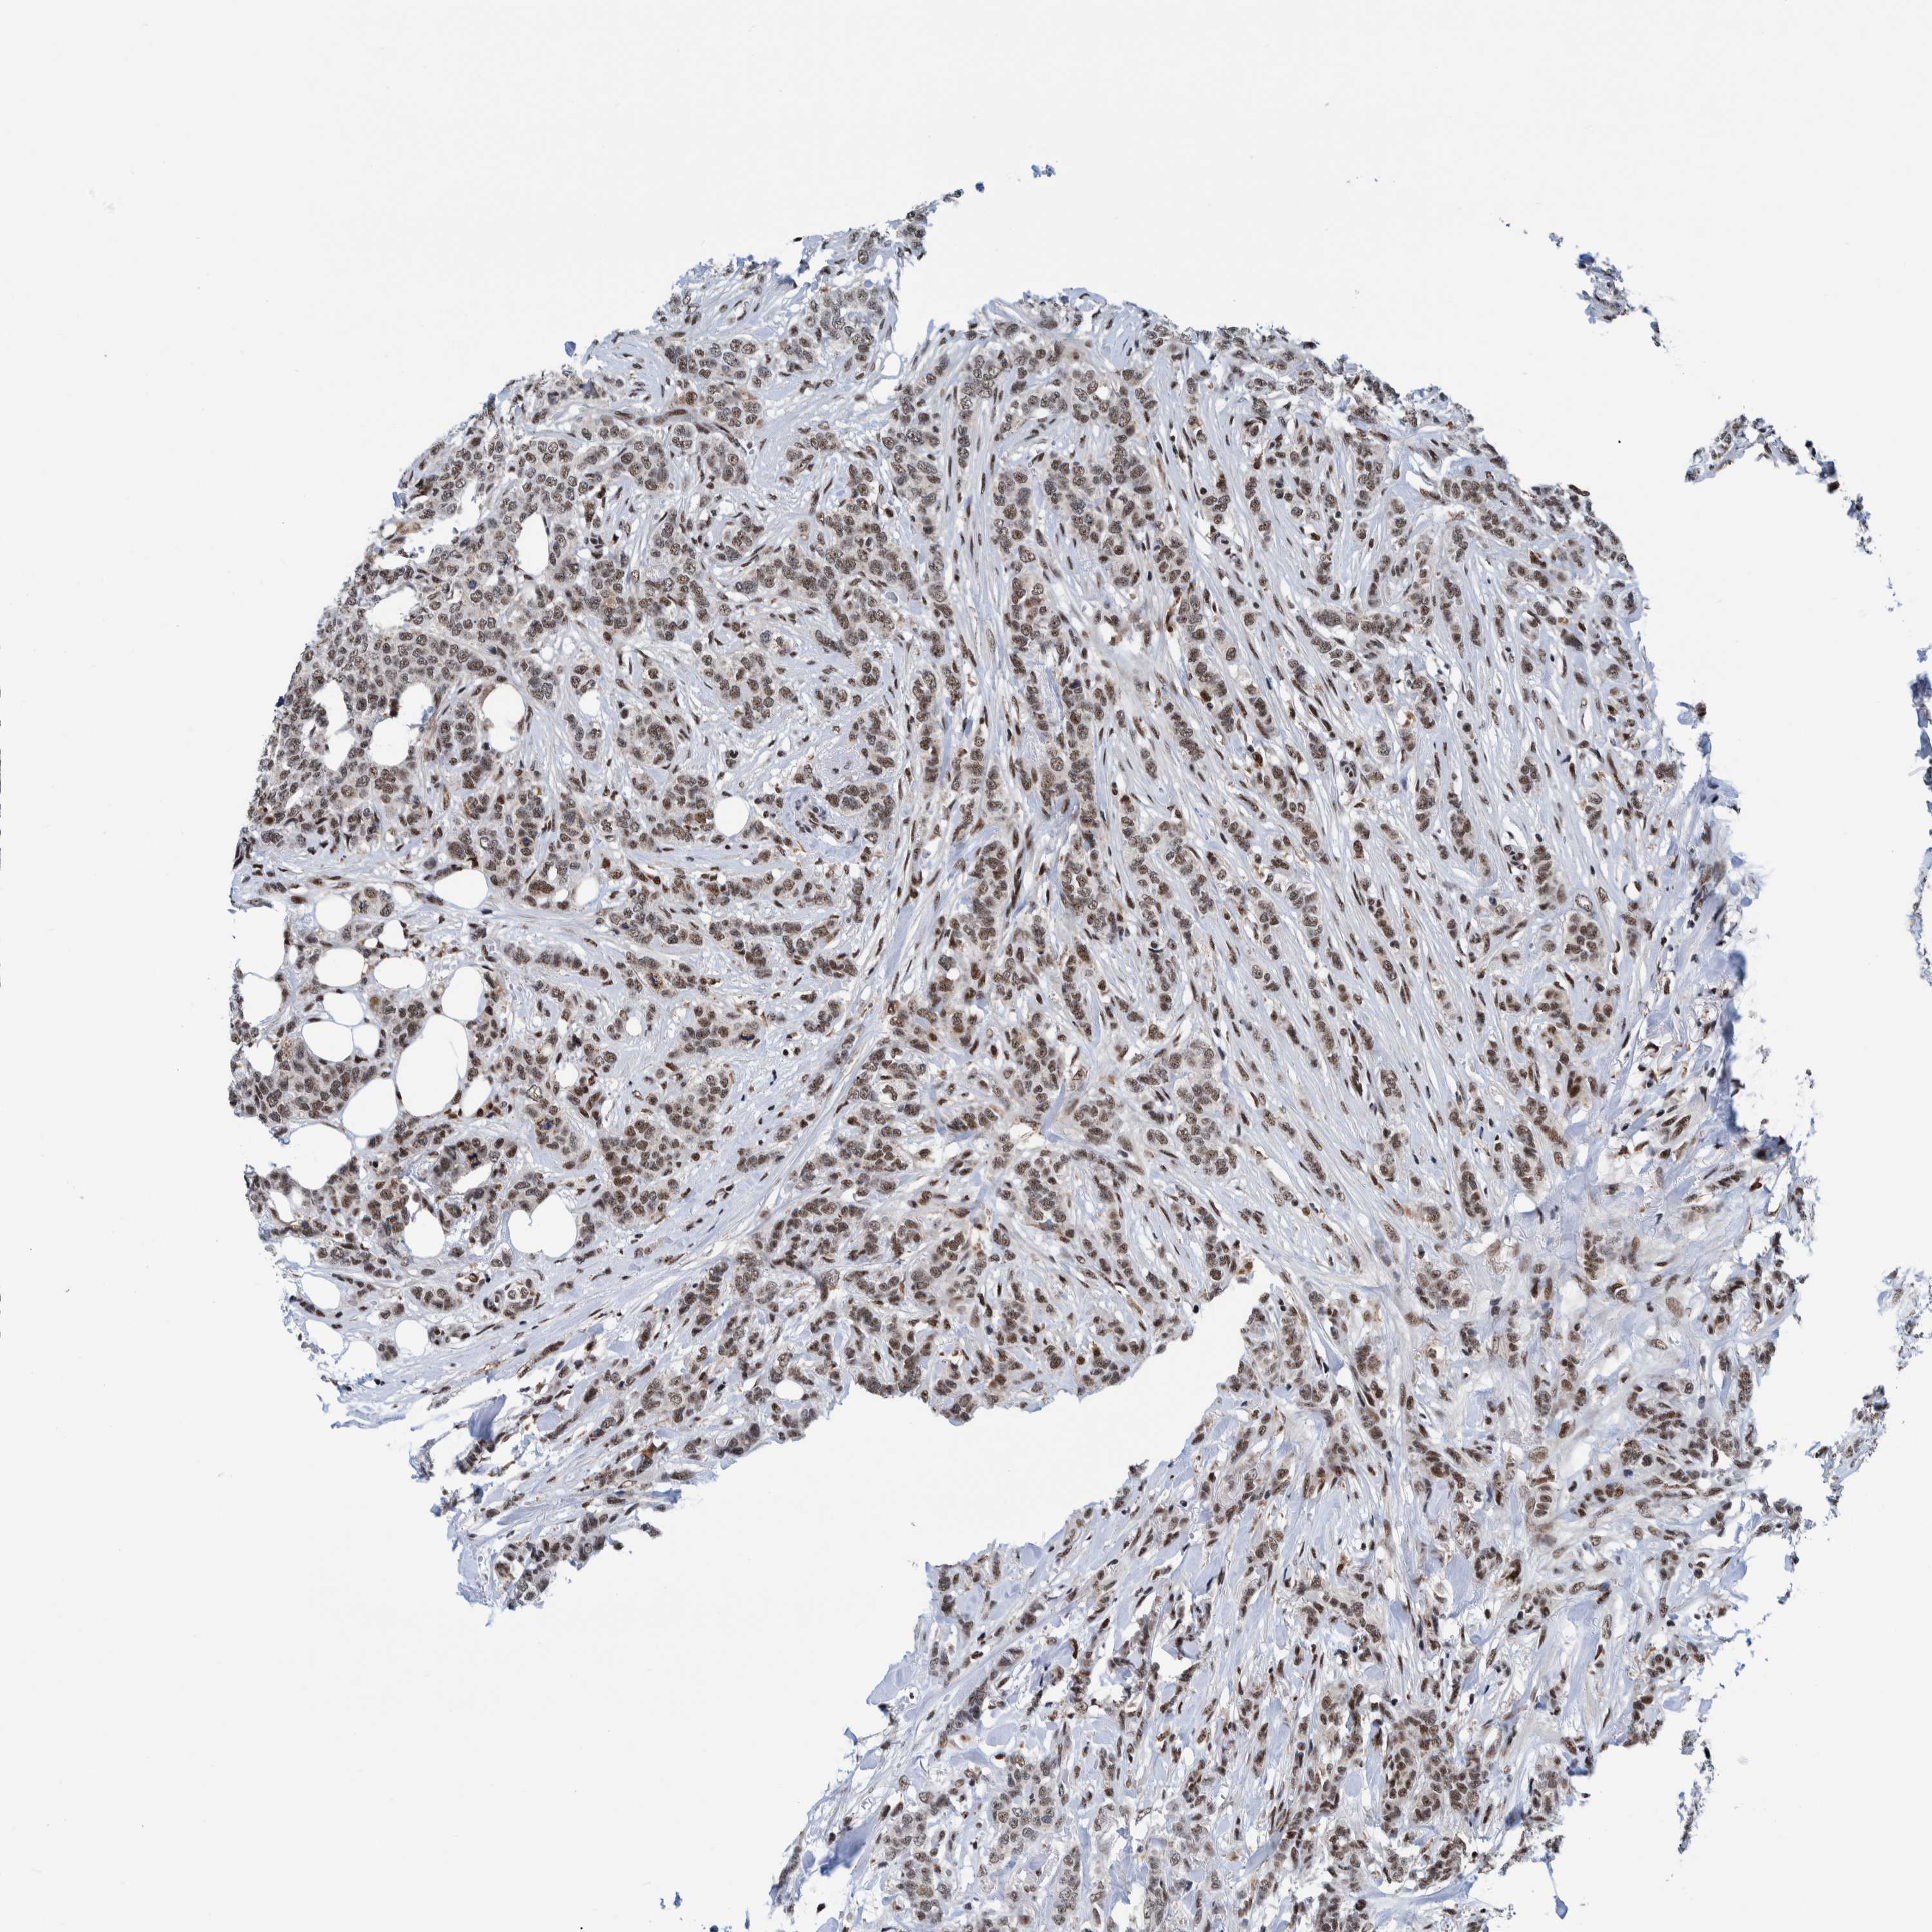

CANCER BREAST CANCER Show tissue menu

BRCA TCGA BRCA VALIDATION PROTEIN EXPRESSION